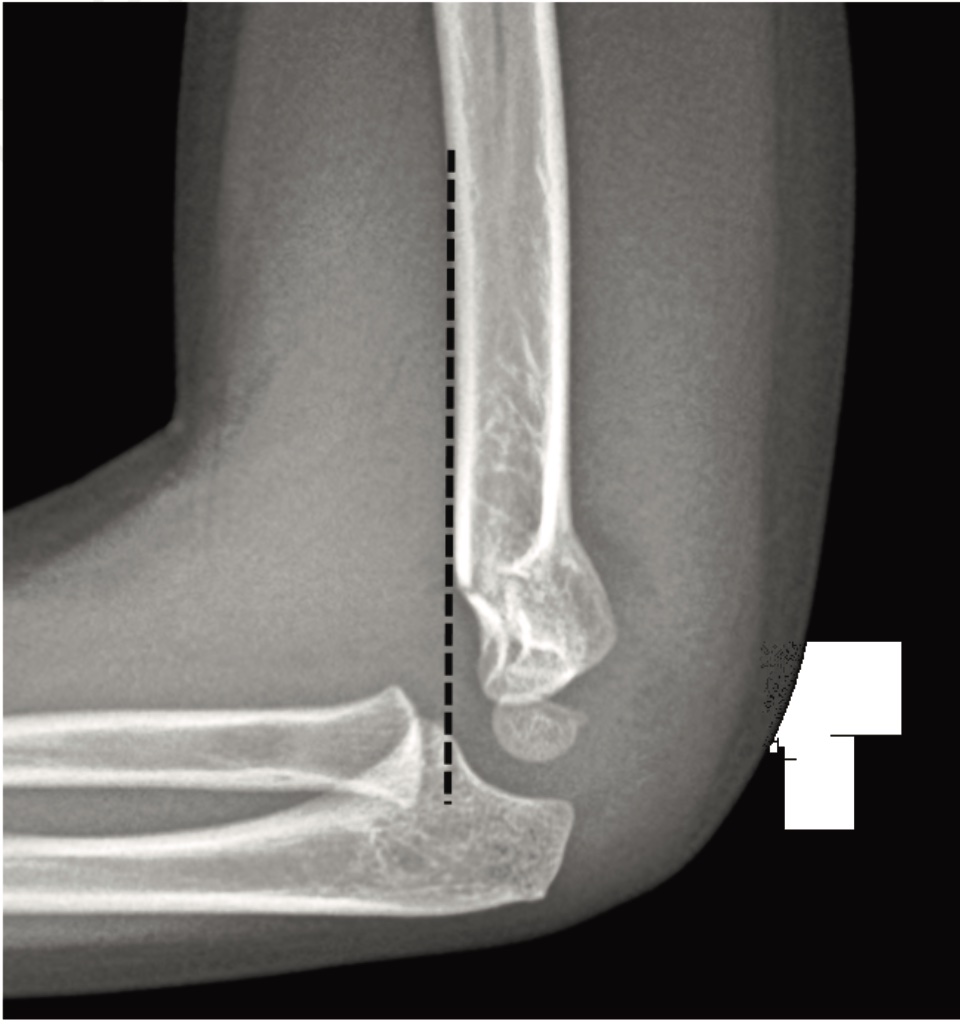

humeral line anterior elbow supracondylar pediatric fractures normal radiology fracture humerus radiopaedia capitellum angle capitulum joint case types injuries occult

elbow ray radial fracture head normal alignment line anterior humeral coreem

elbow forearm normal lateral alignment anterior capitellum radiograph interpreting radiographs fracture supracondylar intersect

elbow line anterior normal radiocapitellar humeral fractures adults lateral radiograph dislocations imaging

humeral radiocapitellar elbow radiographic

elbow humeral fracture supracondylar forearm capitellum radiographs interpreting intersect

radiopaedia line humeral anterior radiology

capitellum dislocation elbow pediatric through drawn lateral anterior humeral pass should line

Anterior humeral line. Pediatric humeral fracture. Elbow injuries